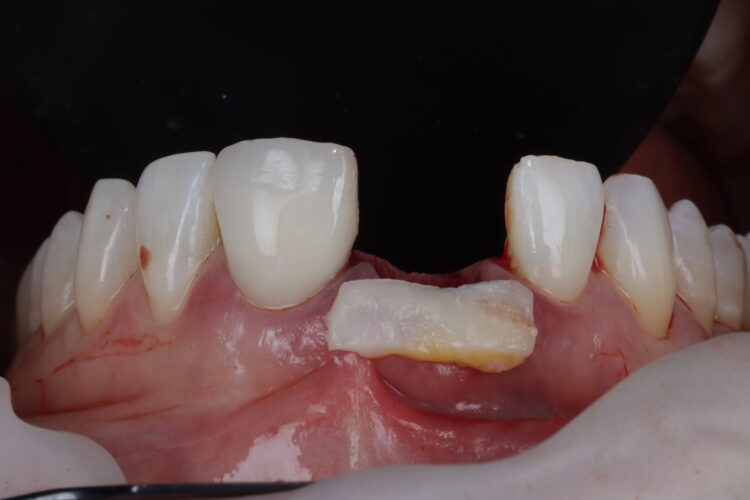

On the day of surgery, the post crown was removed, and the tooth sectioned to ease extraction while preserving the buccal plate. Forceps were used to deliver the fragments, with extensions to simplify pick-up (Hu-Friedy). The granulation tissue was removed using a Lucas curette.

The surgical guide was checked in the mouth, ensuring it was fully seating and not in contact with the adjacent teeth.

A bone graft was then performed, adding MinerOss® Blend (BioHorizons Camlog) to the jump gap. This affords an ideal combination of cortical and cancellous bone, delivering high bone density and reliable revascularisation to ensure the fast and predictable turnover of bone.

The temporary restoration was then reintroduced and the surgical site closed tension-free. Vertical sling sutures were placed through both papillary areas over the contact points to hold the tissue up, create a prosthetic sealand to combat natural shrinkage.